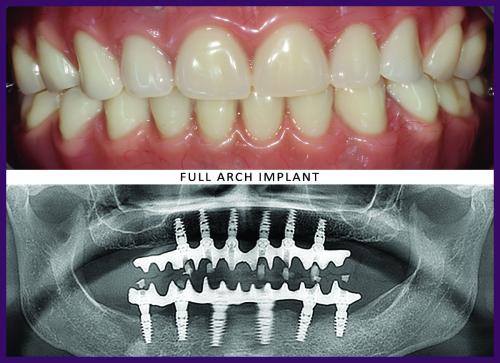

When all of the teeth are missing, a person’s life can become miserable. Aside from chewing and speaking problems, the person’s jawbone starts deteriorating too. Traditional dentures do provide a solution, but they do not help to stop bone loss. Implant supported dentures are a way to replace teeth when all of the teeth are missing in the upper or lower jaw. In the upper jaw, usually 6 implants are required, whereas for the lower jaw, 4 implants are sufficient. There are two types of implant supported dentures available-one which can be removed by the patient, one that cannot be removed by the patients. Ridgetop Dental’s experts can suggest you the implant supported dentures in Northern Virginia, best suited for your case.